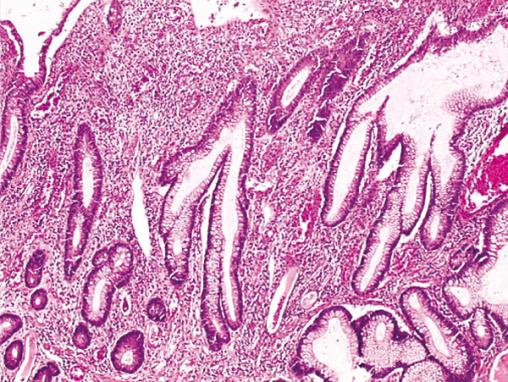

Coll. Pr JF Fléjou, hôpital Saint-Antoine, Paris. Anomalies de l'architecture des glandes (distorsions, ramifications) au cours d'une rectocolite hémorragique